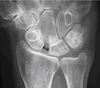

Ruka na obrázku není moje, ale přesně takhle to vypadá.